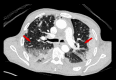

BACKGROUND Coronavirus disease 2019 (COVID-19) caused by severe acute respiratory syndrome coronavirus 2 (SARS-CoV-2) primarily affects the lungs but can involve any organ. The medical community is struggling to cope with the critical illness associated with the disease. On top of that, patients who have recovered from COVID-19 have presented with complications such as thrombotic episodes in various organs both during and after being infected with SARS-CoV-2. A COVID-19-associated prothrombotic state has been mentioned in multiple recent research articles. The role of anticoagulants is debatable, because even after receiving them prophylactically, many patients have experienced thrombotic episodes. The situation, therefore, represents a challenge to the medical community. CASE REPORT We report on a COVID-19-associated prothrombotic state in a 65-year-old man with no history of comorbid illness. Initially, he presented with right-sided weakness and was found to have had an acute ischemic stroke. Urgent imaging after the stroke revealed changes on electrocardiography that were remarkable for left bundle branch block. The patient's elevated cardiac enzyme levels correlated with a silent acute myocardial infarction (MI). His echocardiogram revealed a left ventricular (LV) thrombus. He was managed with a multidisciplinary approach involving Neurology, Cardiology, and Medicine. CONCLUSIONS COVID-19-associated prothrombotic episodes involving arterial and venous systems have been reported in the literature. But concomitant stroke, acute MI, and LV thrombus rarely have been documented. The role of prophylactic or therapeutic anticoagulation is still unclear because even when patients are on these drugs, they continue to develop thrombotic episodes. Indeed, further studies are required to develop a standard management plan for what can be a fatal situation.